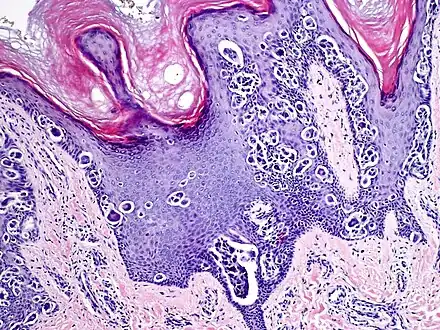

An acral nevus is a cutaneous condition of the palms, soles, fingers, or toes (peripheral body parts), characterized by a skin lesion that is usually macular or only slightly elevated, and may display a uniform brown or dark brown color, often with linear striations.[1]: 1726

They are brown to dark brown in color and have linear streaks of darker pigmentation. Size is usually 7 mm or less, oval or spindle shaped, and well-demarcated. They become stable after an initial growth phase, and the number of lesions also decreases; a new lesion in middle-aged or elderly people should raise suspicion of acral lentiginous melanoma.

Melanocytic acral nevus with intraepidermal ascent cells (MANIAC)